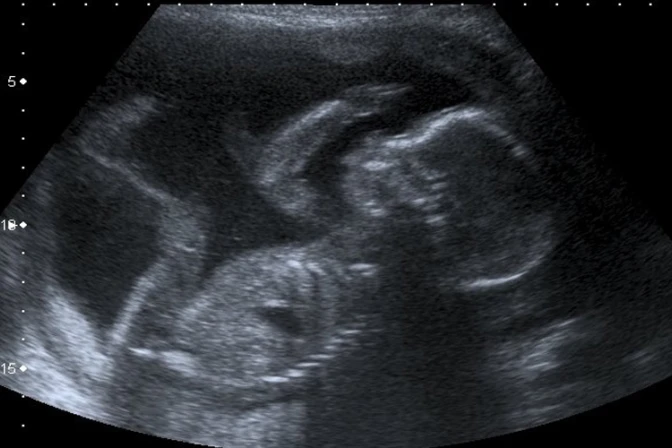

Entre las diversas intenciones que han recibido, May Feelings puso como ejemplo la de una mujer identificada como Elina, embarazada de 28 semanas a quien le han diagnosticado cáncer de cuello uterino. Ella quiere tener a su hijo pero los médicos le han dicho que aborte para salvar su vida. Esta madre pide a todos que recen por su intención.